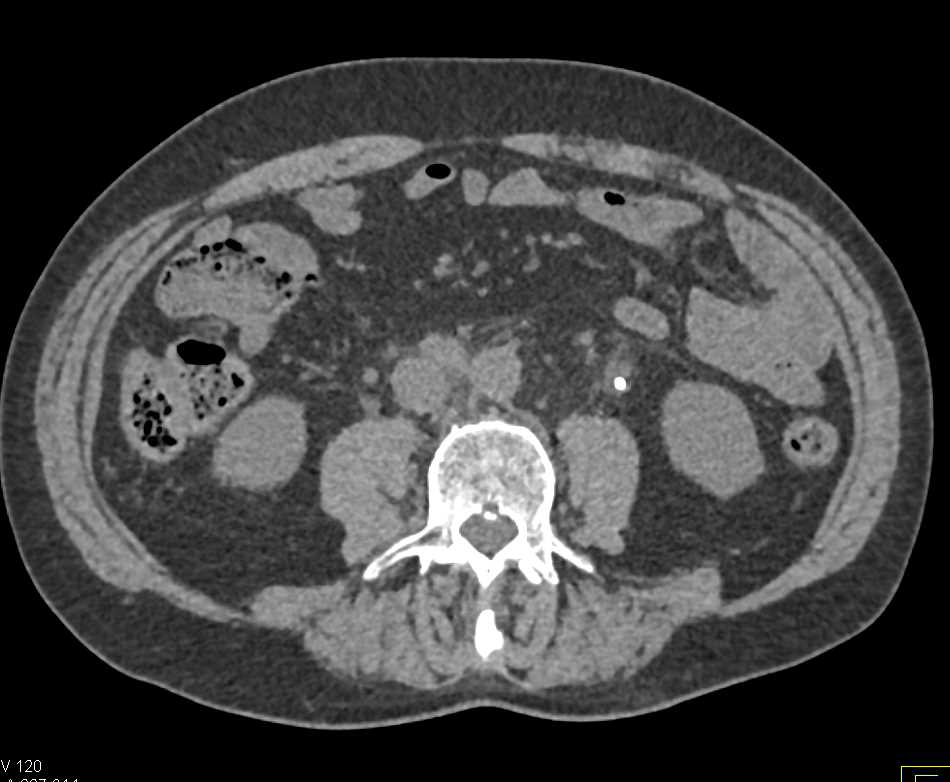

Necrotic Pelvic Nodes as well as Left Psoas Infiltration and Beyond